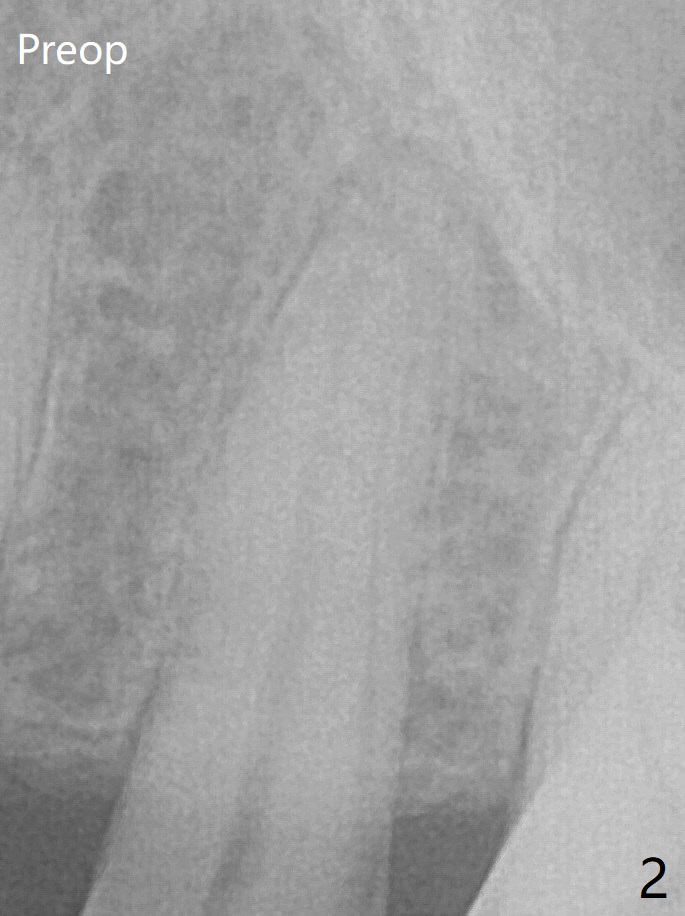

The coronal lamina dura becomes indistinct 5 months postop (Fig.6). The bone graft remains in the socket. There appears no bone graft loss. Great? Ready for implant placement? What is the next step?